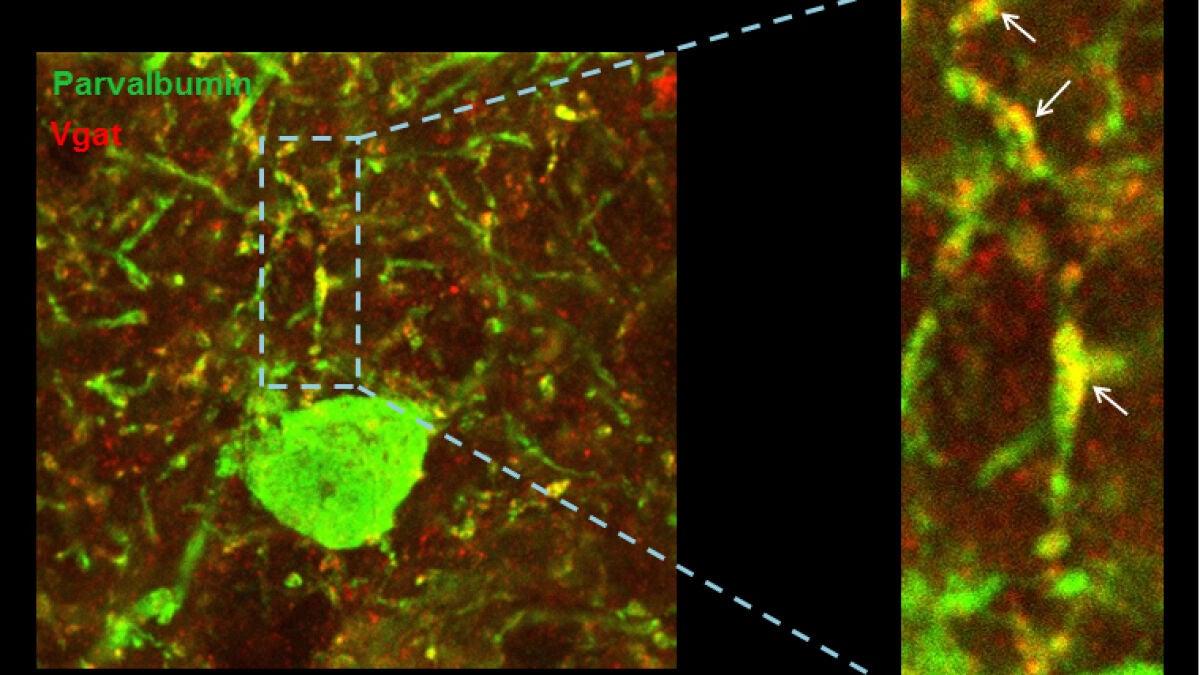

Las científicas se han centrado en uno de los genes relacionados con el síndrome de Down. Mediante experimentos con modelos animales que sobreexpresan el gen candidato, demostraron que el exceso de este gen provoca cambios muy sutiles en el equilibrio excitación/inhibición y estos llevan a una reducción notable de la actividad y sincronización de las neuronas excitadoras en la corteza prefrontal.

Es decir, que cuando este gen se encuentra sobreexpresado, reduce el nivel de descarga de las neuronas y altera el ritmo en las ondas de alta frecuencia de la corteza cerebral. Es más, observaron que el problema radica en unas neuronas que se encargan de controlar la inhibición. En resumen, si hay menos actividad y existe una desequilibrio en las frecuencias de las ondas cerebrales en síndrome de Down es debido a cambios en la conectividad de las neuronas que deben controlarlas.

El estudio ha combinado experimentos de electrofisiología e histología con un modelo computacional que emula el circuito neuronal de la corteza cerebral de forma virtual. “Hemos identificado alteraciones anatómicas y funcionales, y a través de un modelo computacional hemos demostrado cómo dichos déficits pueden explicar las observaciones experimentales” comenta Sánchez Vives, jefe del equipo de Neurociencia de Sistemas y coinvestigadora principal del estudio.